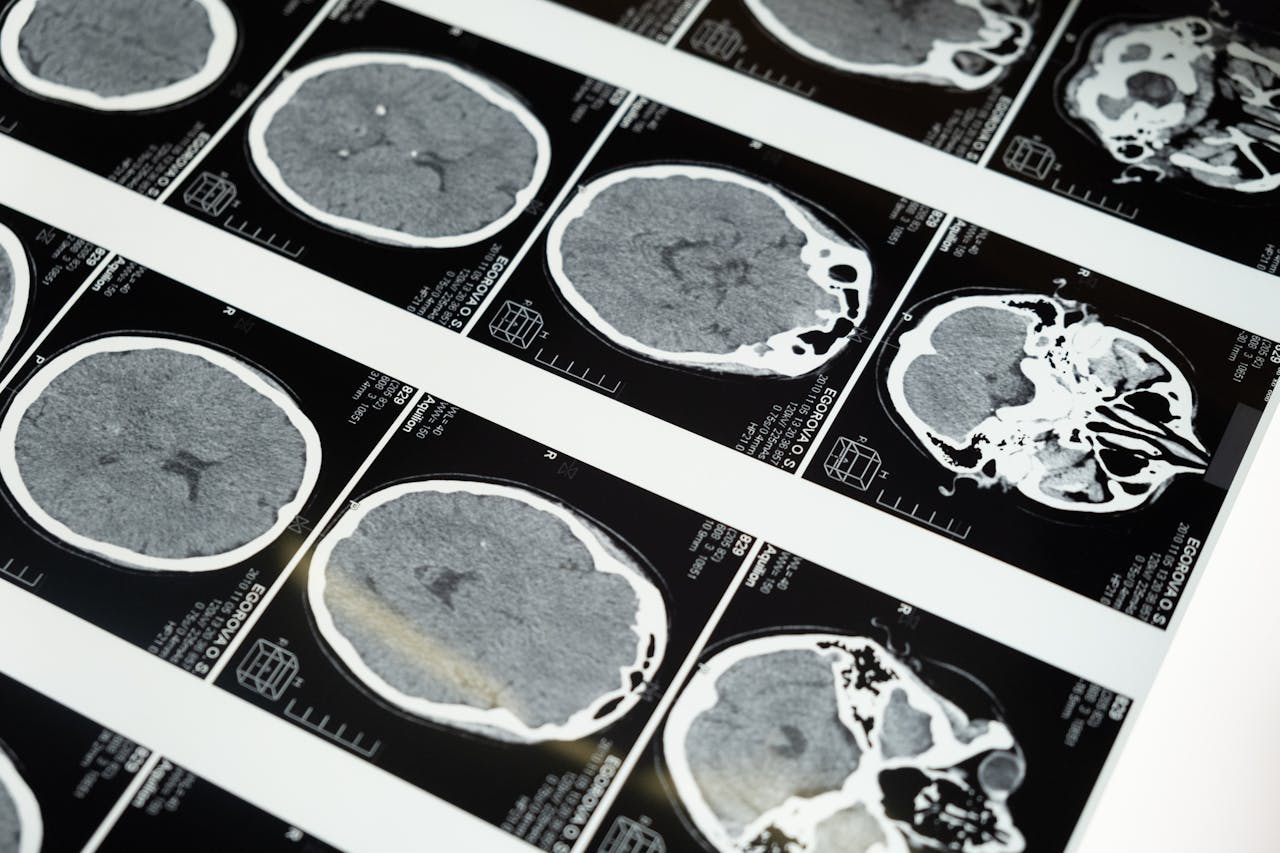

- Prise en charge chirurgicale de pathologies crâniennes.